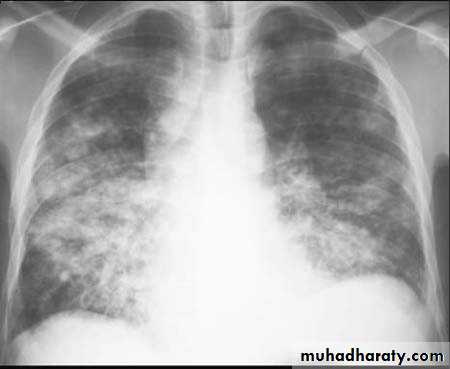

Lobular consolidation ( broncho pneumonia )

Very important to consider that pulmonary edema in normal sized heart have close similar appearance to broncho pneumonia

The important Golden Key differentiation is the cardiac size being enlarged in pulmonary edema .

Post primary TB broncho pneumoniacotton wool sign

Post primary TB Bronch pneumonia

36.lobuler consolidation (lobular pneumonia )37.discussion